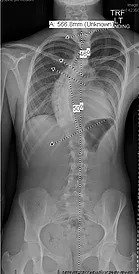

Adolescent Idiopathic Scoliosis (Type 2)

14 yr girl